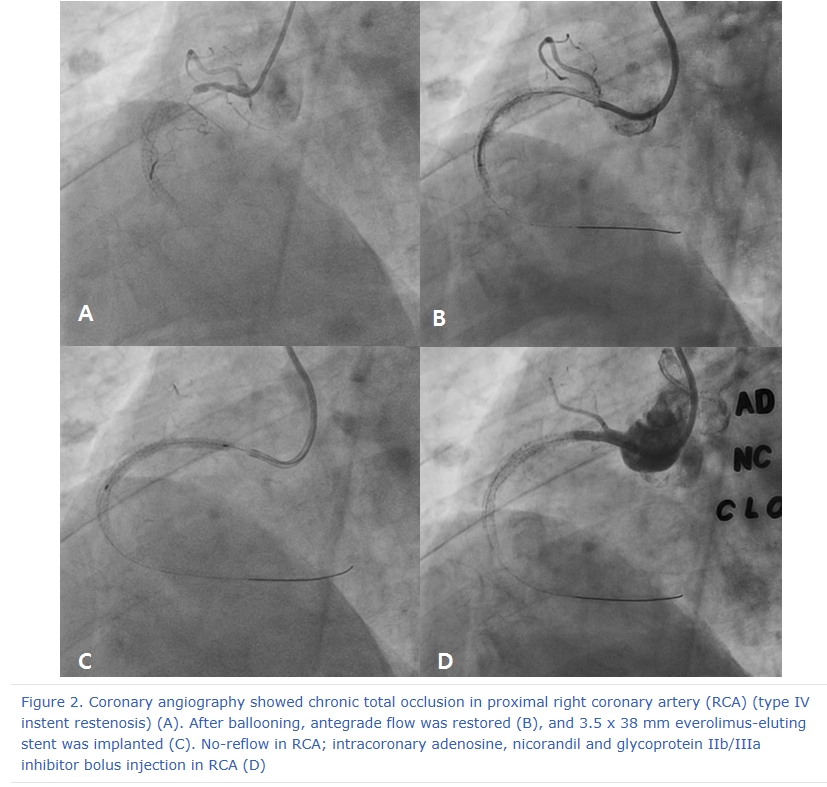

A 78 year-old male visited the outpatient department of Chonnam National University Hospital with intermittent chest pain for 4 months. He underwent percutaneous coronary intervention (PCI) for acute myocardial infarction (AMI) using bare metal stent in the proximal right coronary artery (RCA) 8 years ago. After that, he had undergone repeat intervention using drug eluting ballooning 7 years ago and PCI for mid RCA 6 years ago due to repeated in-stent restenosis (ISR) in RCA. He was treated with dual anti-platelet therapy of aspirin (100 mg daily) and clopidogrel (75 mg daily). Recently, he suffered from chest pain intermittently and was taken to our hospital. The 12-lead electrocardiogram showed normal sinus rhythm and left bundle branch block (no interval change) (Figure 1), and the level of cardiac enzymes were within normal range. He underwent elective coronary angiography (CAG), and it revealed chronic total occlusion in proximal RCA (Type IV ISR) (Figure 2A) with moderate stenosis in proximal left descending artery (LAD). We considered to do staged PCI for proximal LAD. After wiring into RCA with microcatheter backup, stepwise ballooning using 1.5 mm and 2.5 mm diameter balloon was done. Then, a 3.5 x 38 mm everolimus-eluting stent (Xience Alpine®) was implanted at proximal RCA (Figure 2B). Just after stenting with up to 10 atmospheres, no reflow below the lesion site was shown on follow-up CAG (Figure 2C). Coronary blood flow was not restored after intracoronary adenosine, nicorandil and glycoprotein IIb/IIIa inhibitor bolus injection in RCA (Figure 2D). Although we did additional ballooning from distal to proximal RCA again and again (Figure 3A), follow-up CAG showed still no reflow in RCA (Figure 3B). So, we infused intracoronary adenosine and nicoradil using microcatheter from proximal to distal RCA selectively (Figure 3C). Final CAG showed improved antegrade flow (TIMI III) in RCA without significant residual stenosis (Figure 3D). He was transferred to coronary care unit and monitored with anticoagulation for 1 day.

Figure 2. Coronary angiography showed chronic total occlusion in proximal right coronary artery (RCA) (type IV instent restenosis) (A). After ballooning, antegrade flow was restored (B), and 3.5 x 38 mm everolimus-eluting stent was implanted (C). No-reflow in RCA; intracoronary adenosine, nicorandil and glycoprotein IIb/IIIa inhibitor bolus injection in RCA (D)